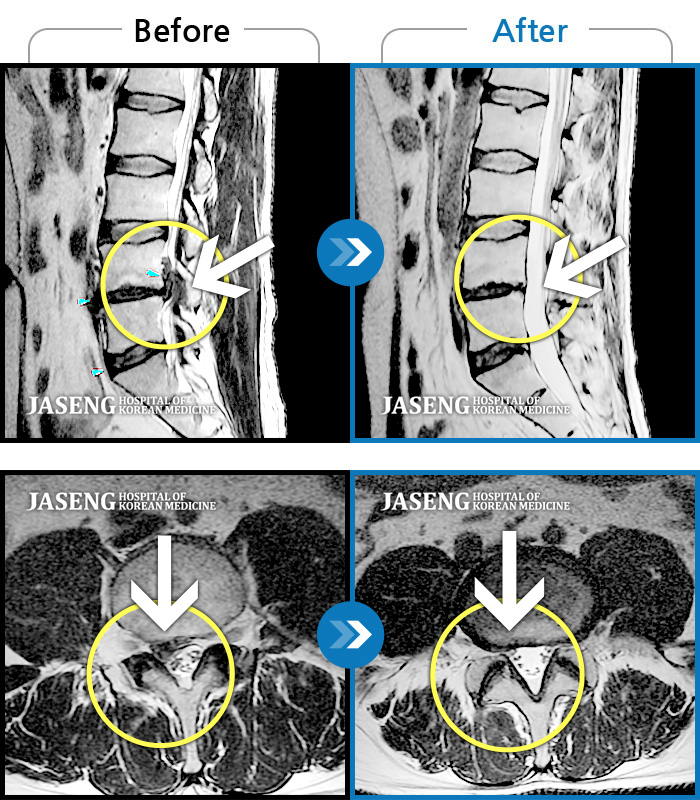

허리디스크

보라매 · 강준규 원장

우측 엉치 부터 발 끝까지 저리고 아픈 증상이 있었다.

촬영시기

2019.02.28 ~ 2020.02.10